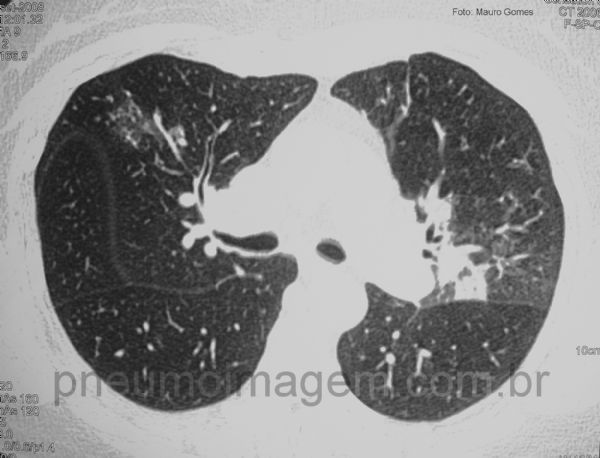

As lesões estendem-se por ambos os lobos superiores e lobo médio, à direita.

Diagnóstico de BOOP (bronquiolite obliterante com pneumonia em organização) confirmado através de biópsia a céu aberto, com achado de pneumonia em organização e doença bronquiolocêntrica.

The lesions extend over both upper lobes and middle lobe on the right.

Diagnosis of BOOP (bronchiolitis obliterans organizing pneumonia) confirmed by open biopsy with findings of organizing pneumonia and bronchiolocentric disease.